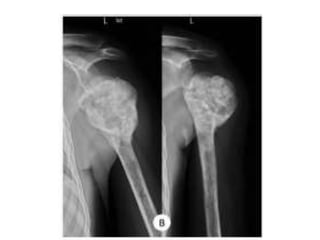

JULY 2009

SEPT 2009

1 year later

CASE 1

CASE 2

CASE 3

CASE 4

CASE 5